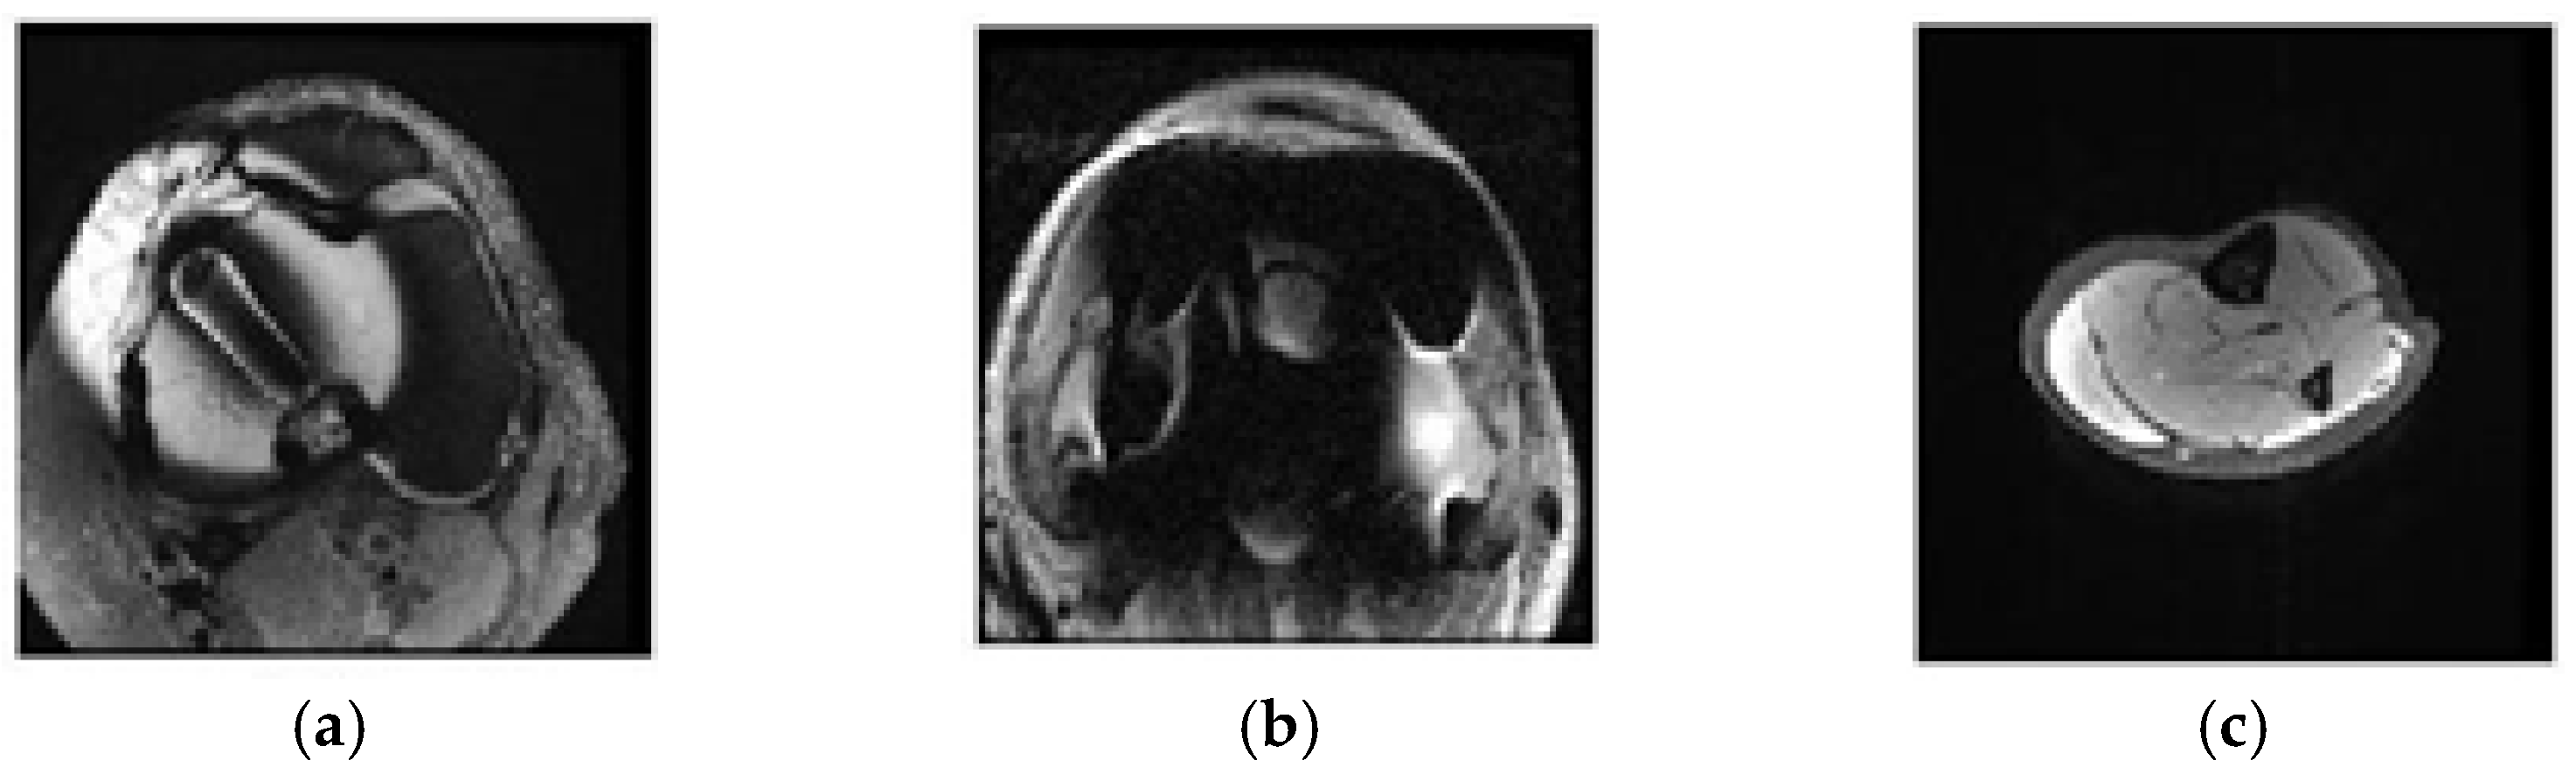

2.3.3. Classification of Axial Images and Results

2.4.3. Selecting Relevant Regions on the Axial Axis